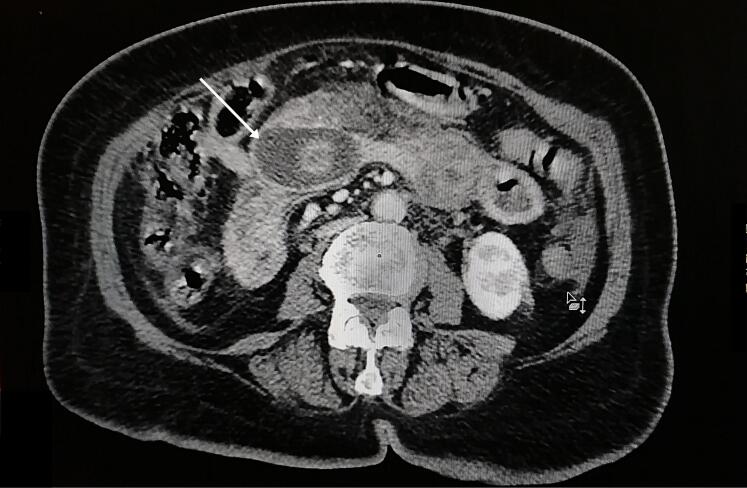

A computed tomography (CT) scan revealed signs of small bowel obstruction due to a jejunal gallstone (Fig. 1). She had pneumobilia due to a cholecysto-duodenal fistula (Fig. 2).

Fig. 1.

CT scan in the axial plane showing pneumobilia (arrow).